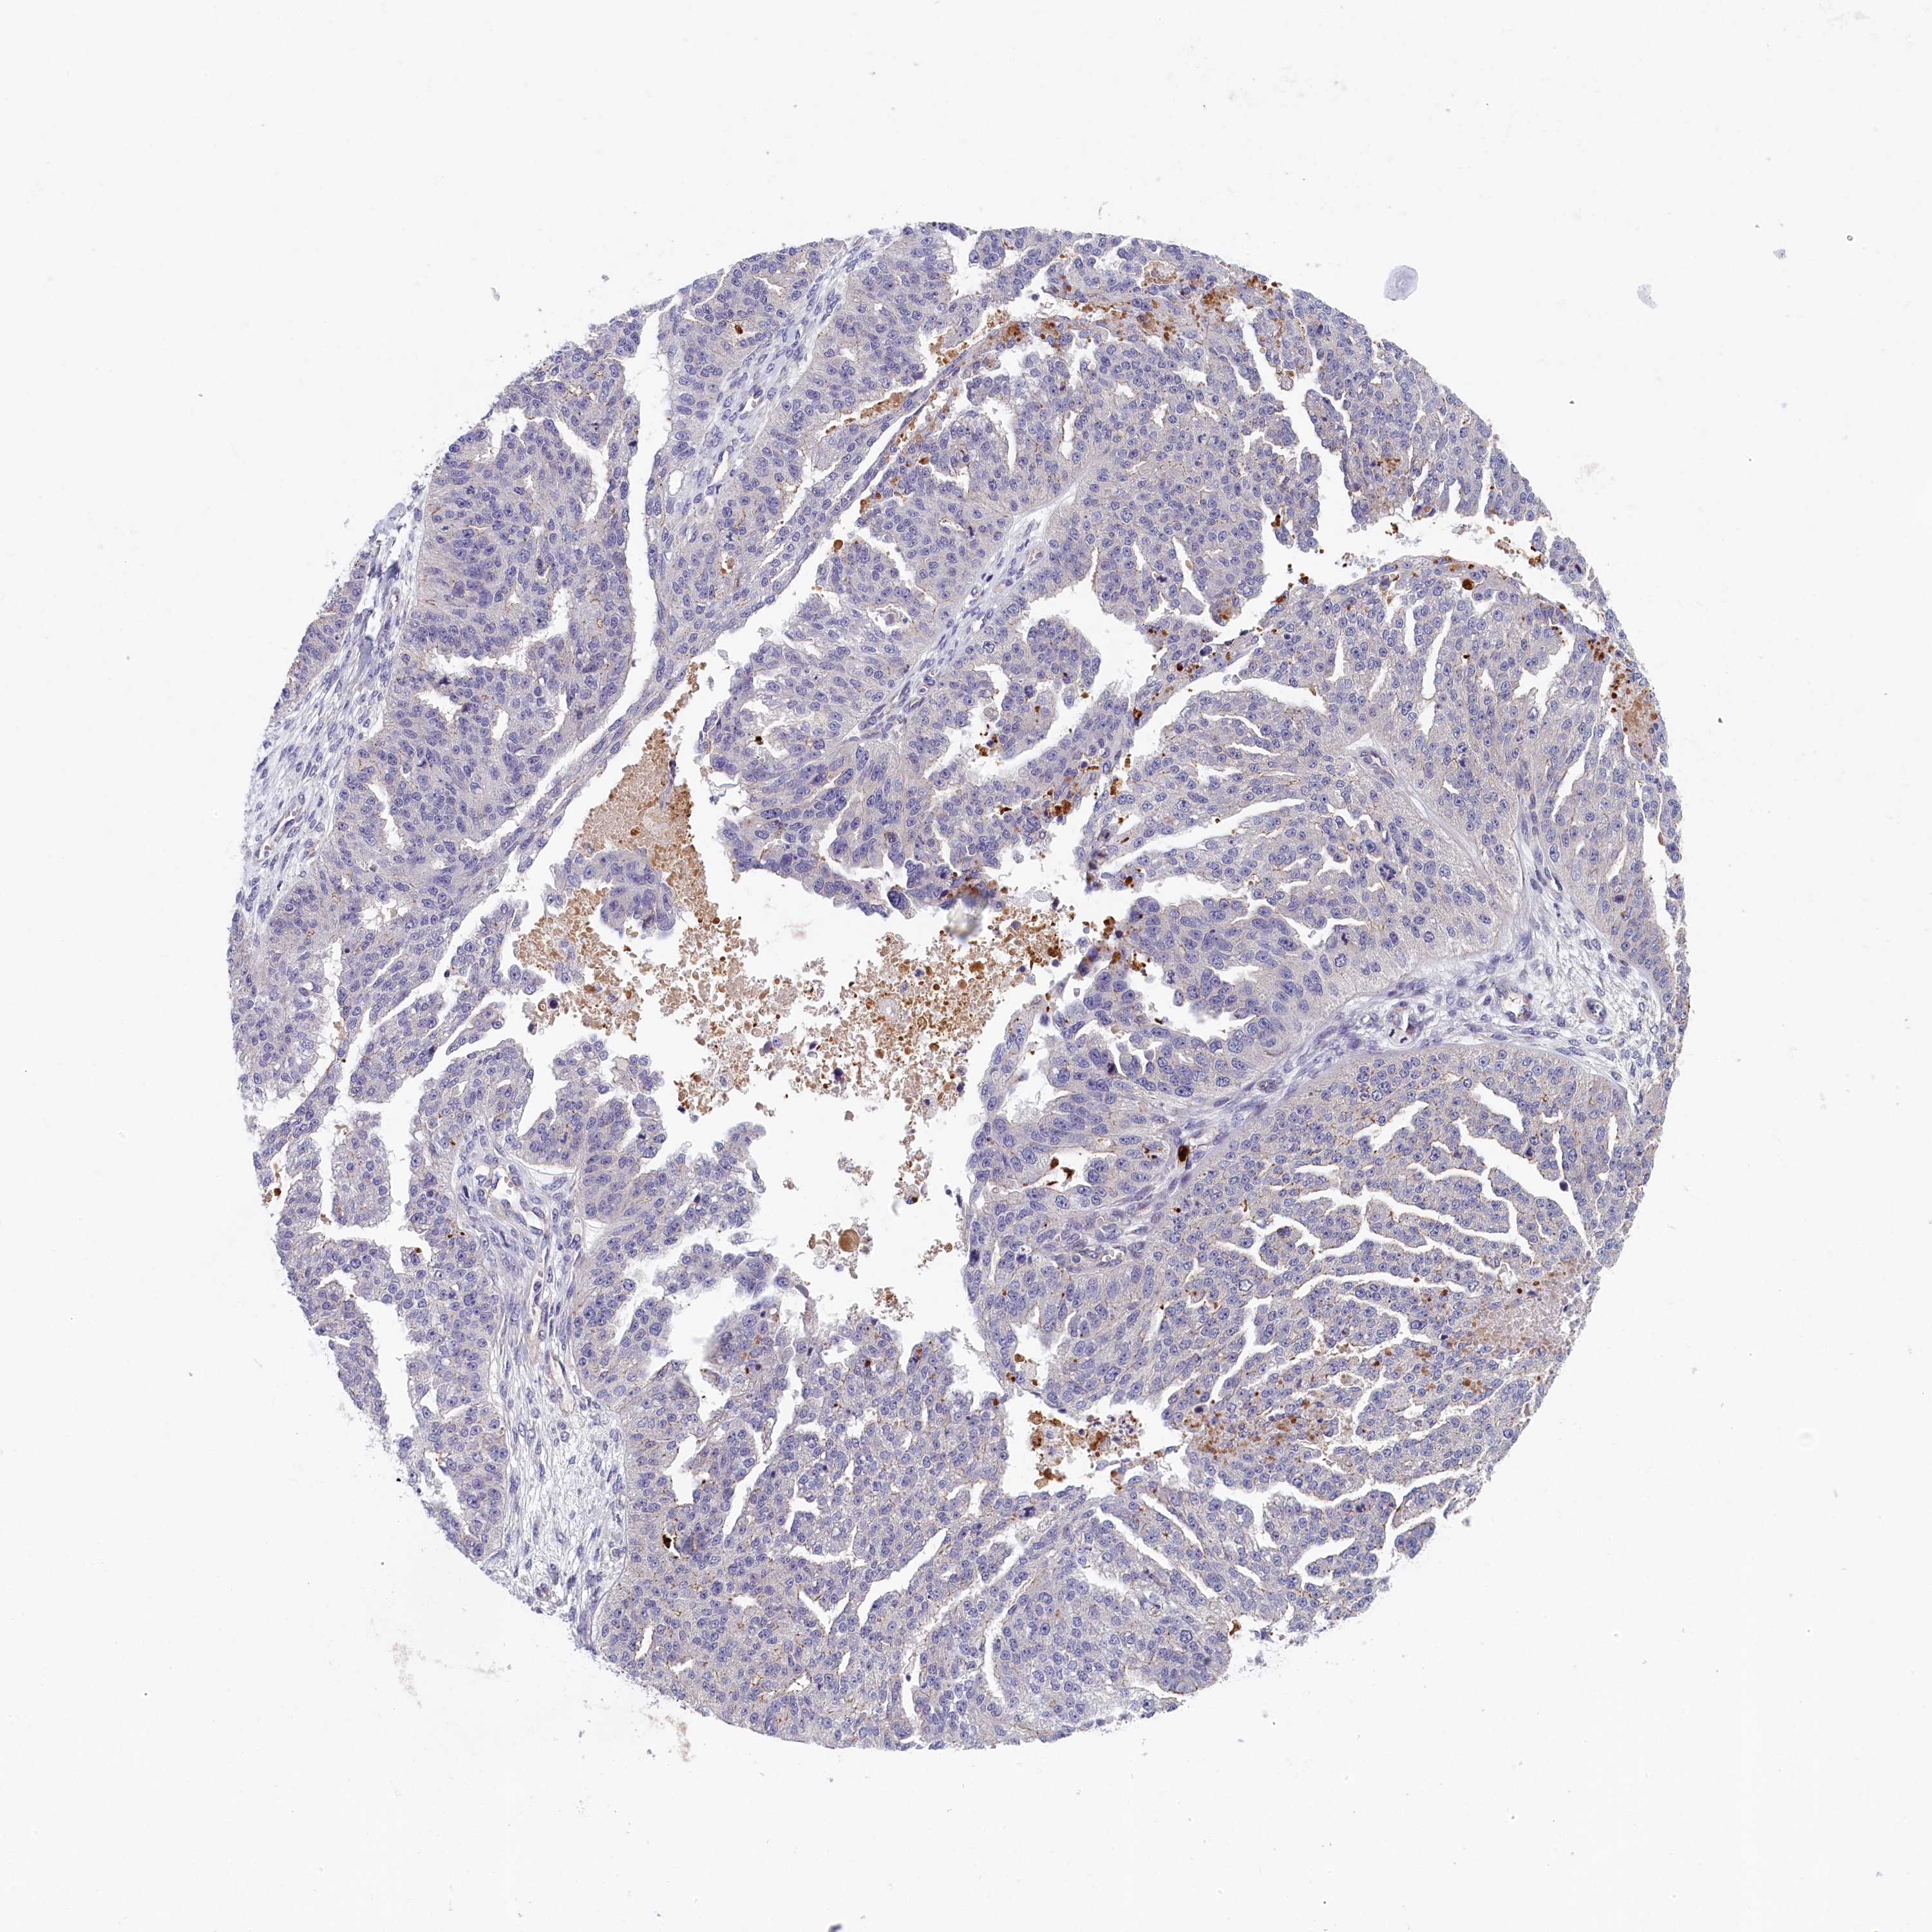

OVARIAN CANCER - Protein expressioni

A mouse-over function shows sample information and annotation data. Click on an image to view it in a full screen mode. Samples can be filtered based on level of antibody staining by selecting one or several of the following categories: high, medium, low and not detected. The assay and annotation is described here.

Note that samples used for immunohistochemistry by the Human Protein Atlas do not correspond to samples in the TCGA dataset.

Antibody stainingi

Antibody staining in the annotated cell types in the current human tissue is reported as not detected, low, medium, or high, based on conventional immunohistochemistry profiling in selected tissues. This score is based on the combination of the staining intensity and fraction of stained cells.

Each image is clickable and will lead to virtual microscopy that enables deeper exploration of all samples and also displays staining intensity scores, fraction scores and subcellular localization as well as patient and tissue information for each sample.

Antibody HPA040824

Cystadenocarcinoma, serous, NOS

Carcinoma, endometroid

Cystadenocarcinoma, mucinous, NOS

Carcinoma, NOS